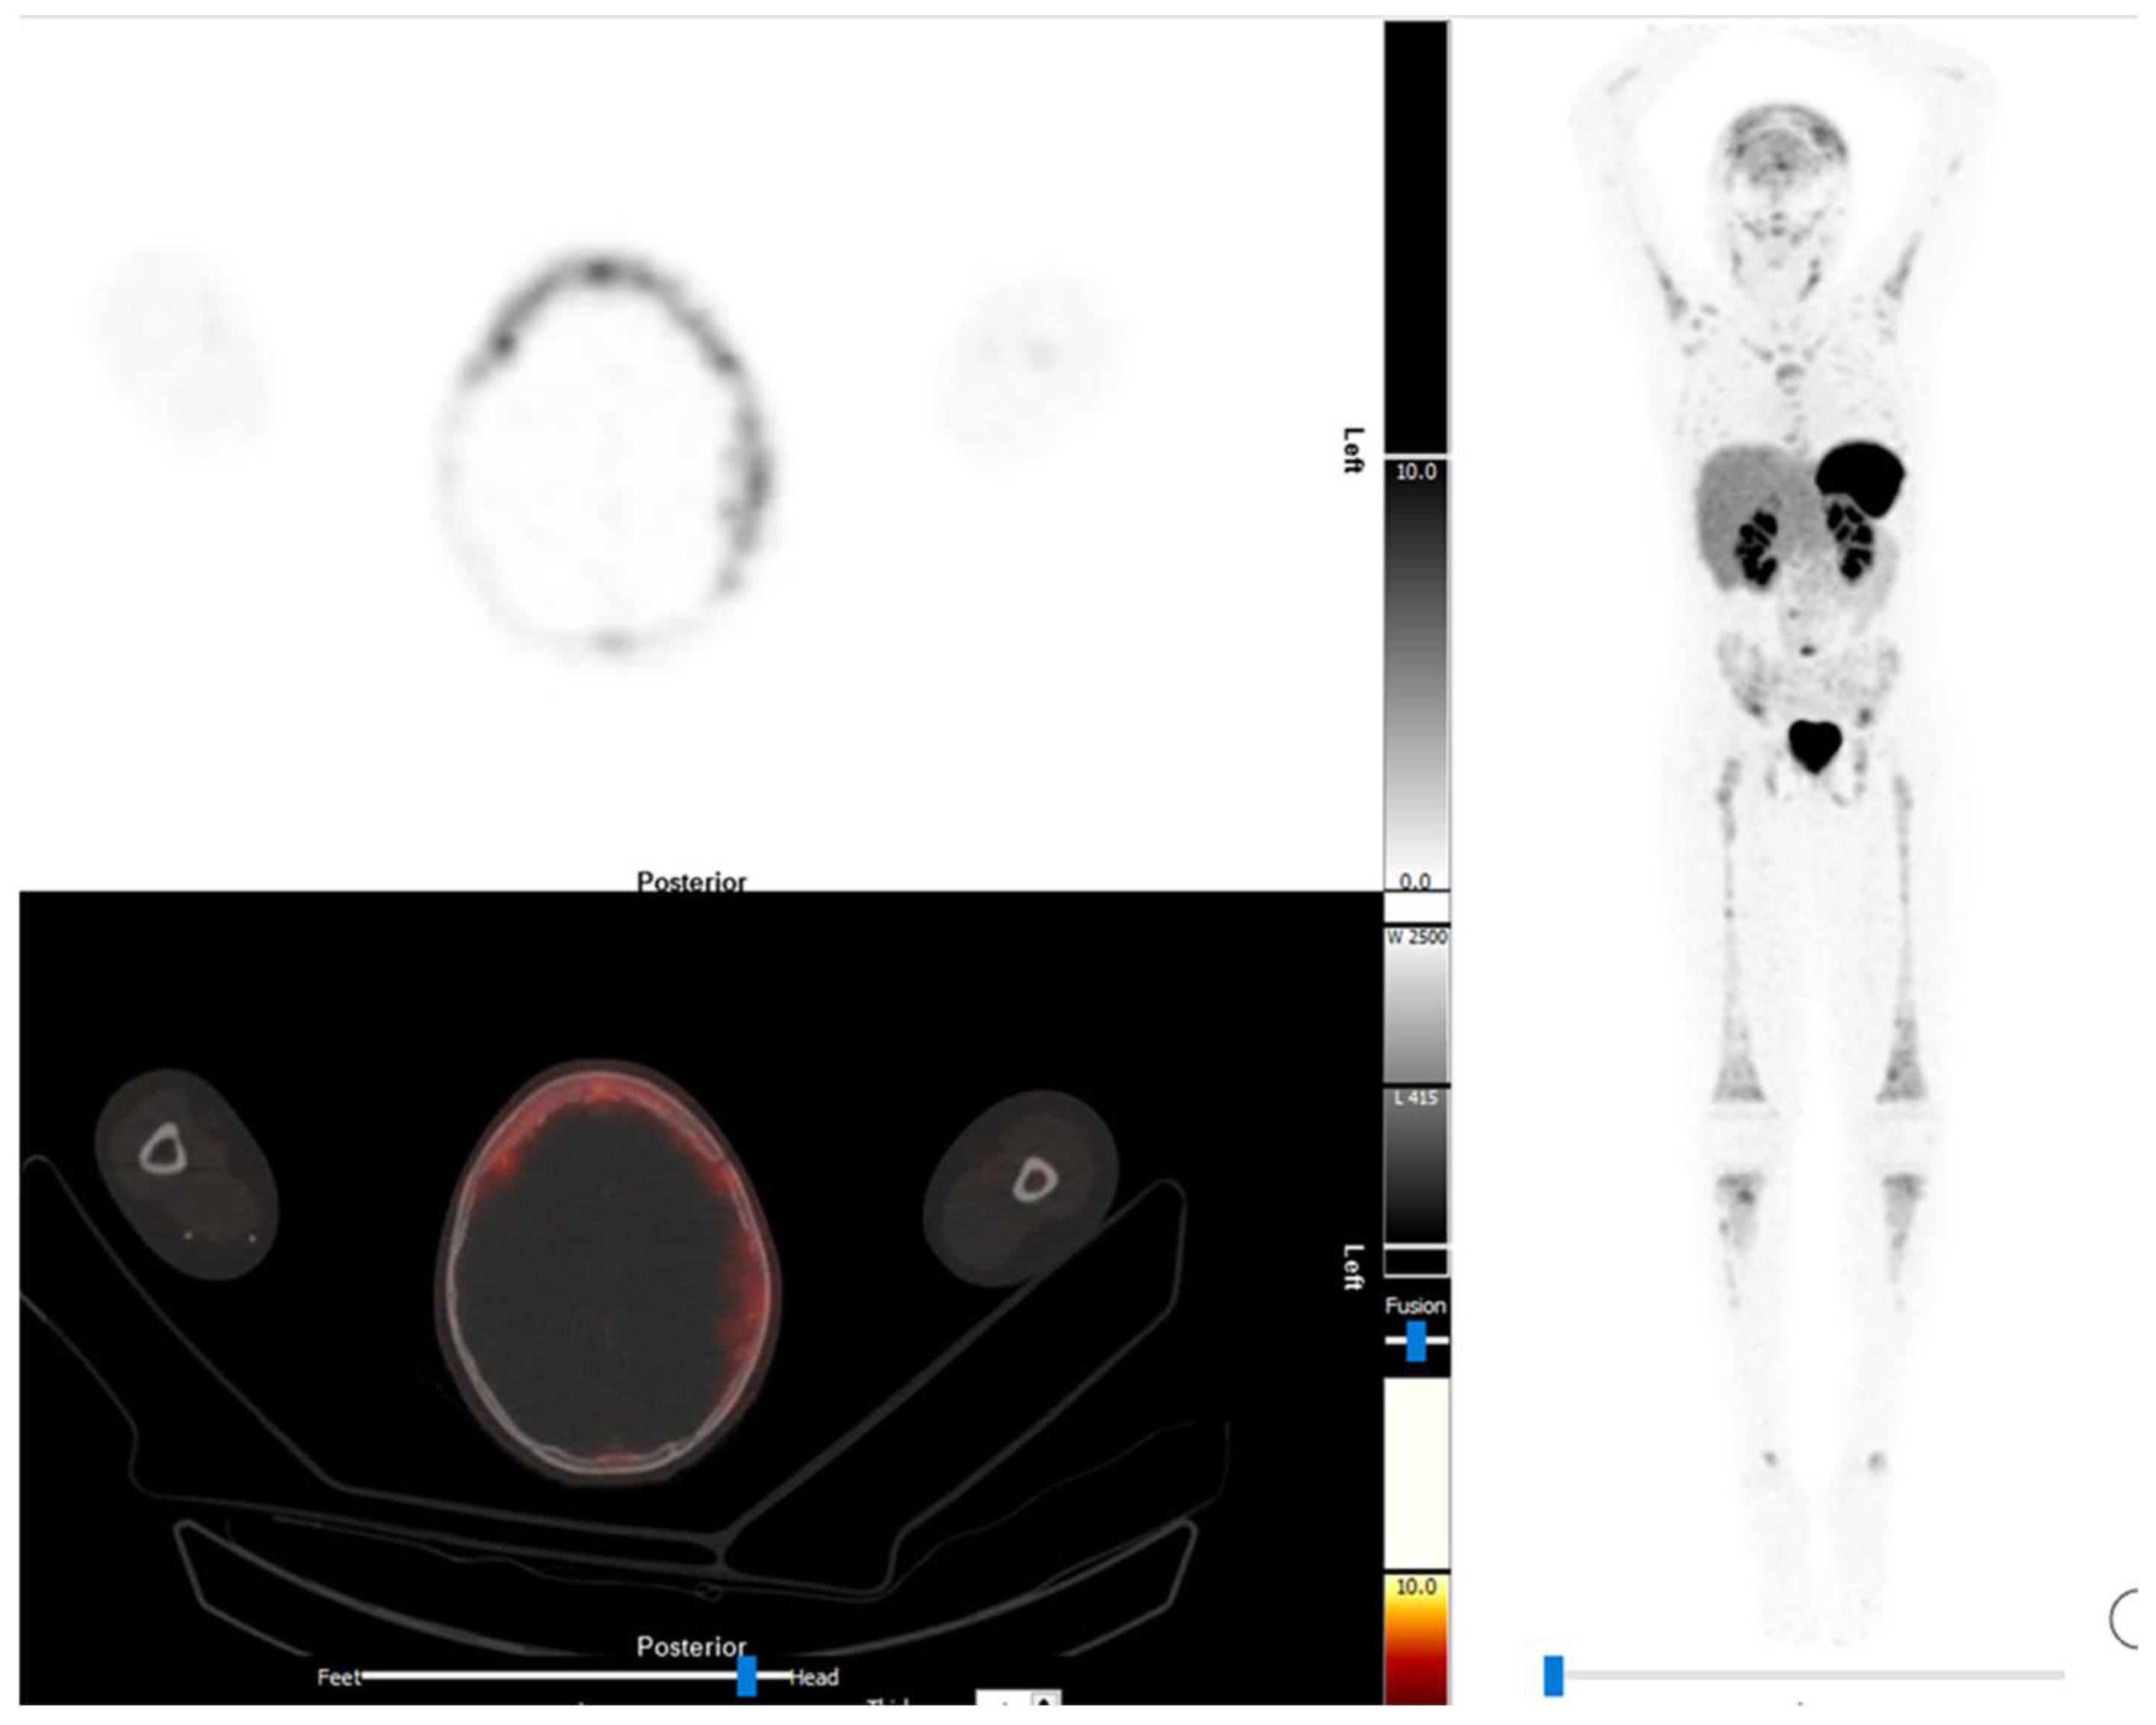

4. Sarcoma

4.1. Osteosarcoma

4.2. Ewing Sarcoma

4.3. Rhabdomyosarcoma

4.4. Nephroblastoma